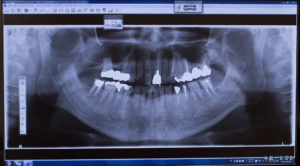

インプラントを長く使用するためには、歯科医院でのメンテナンスも重要です。インプラントを使っていると、徐々に噛み合せが悪くなってくる場合があります。噛み合せが正常ではない場合、様々なトラブルの原因になってしまうため、インプラントを削るなどの修正をおこない噛み合わせを整えることが必要になります。また、見た目にはわからない骨の部分にも異常がないか、X線で撮影して状態を確認することも大切です。インプラントは天然の歯に比べて歯周病のリスクが高いので、定期的に健診を受けるとともに、歯のクリーニングをおこない、ご自身では取り除くことができない歯石や、細菌の集合体である「バイオフィルム」もキレイに除去して、口腔内を清潔に保つようにしましょう。